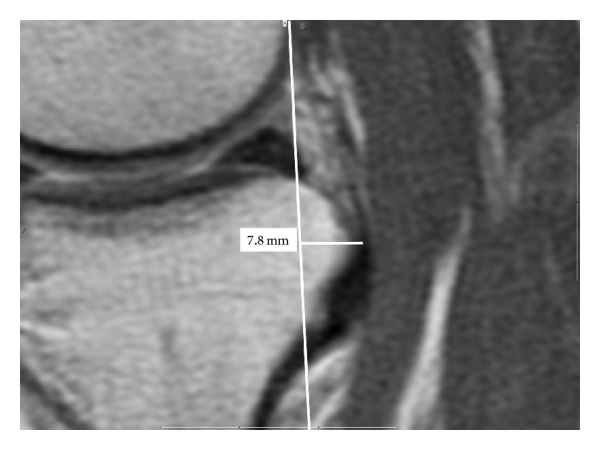

All images were performed on a 1.5 T magnet, using our institutional standard knee MRI protocol. Sagittal PD and fat suppressed T2-weighted fast spin-echo imaging, coronal T1-weighted and fat suppressed T2-weighted fast spin-echo imaging and axial T2-weighted fat suppressed FSE imaging sequences were acquired. Images were obtained with the knee in passive extension. Measurements were performed from the sagittal PD images using the method described by Vahey et al. [2, 3]. Measurements were performed in the midmedial and midlateral compartments independently by two musculoskeletal fellowship trained radiologists for all patients and 18 of 22 controls. On the sagittal image, a tangential line was drawn posterior to the femoral condyle, and another similar line was drawn posterior to the tibia plateau. Perpendicular measurements of the relative anterior or posterior translation were made (Figure 1) for each knee.

(a)

(b)

(c)